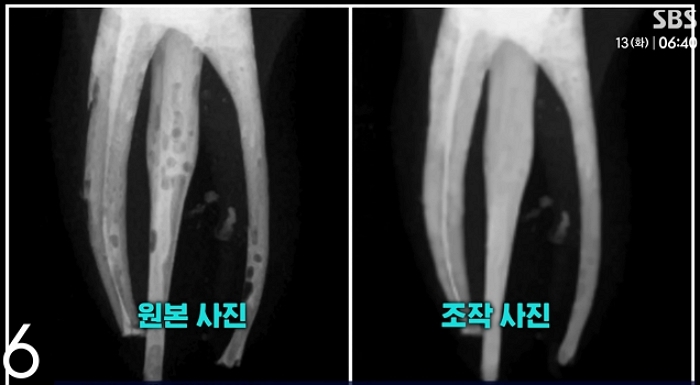

학생들은 신경 치료 과정에서 충전제 주입이 완전하지 않아 엑스레이 촬영 시 기포가 나타나자, 포토샵을 이용해 이를 제거하고 마치 완벽한 치료가 이뤄진 것처럼 결과물을 위조했습니다.

이번 부정행위에 관련된 학생 수는 총 34명에 달합니다. 전체 수강생 59명 중 과반수를 넘는 규모로, 이 중 29명은 직접 사진 조작에 가담했고 나머지 5명은 다른 학생의 조작된 결과물을 표절한 것으로 밝혀졌습니다.